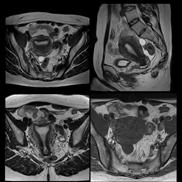

PD STIR - 1024 x 1024 matrix - 3mm slice thickness

Sag T2 - 0.5 x 0.5 min - 0:56 min Ax PD FatSat - 0.6 x 0.6 mm - 1:30 min Cor PD FatSat - 0.6 x 0.6 mm - 1:15 min Cor PD - 0.5 x 0.5 mm - 0:58 min © 2020 CANON MEDICAL SYSTEMS // MREU200040

Fast knee protocol with AiCE on Vantage Orian 1.5T